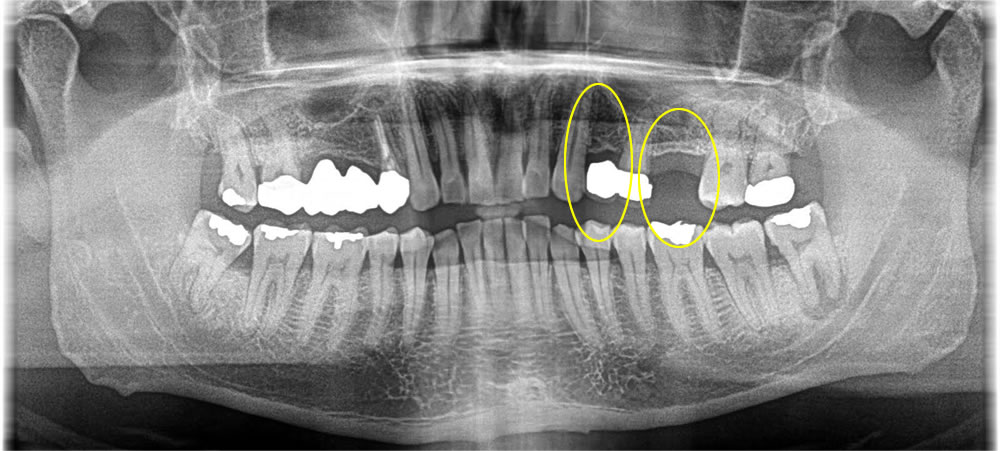

破折歯を抜歯即時埋入インプラントで治療した症例

年齢

50代

性別

女性

症例を見る